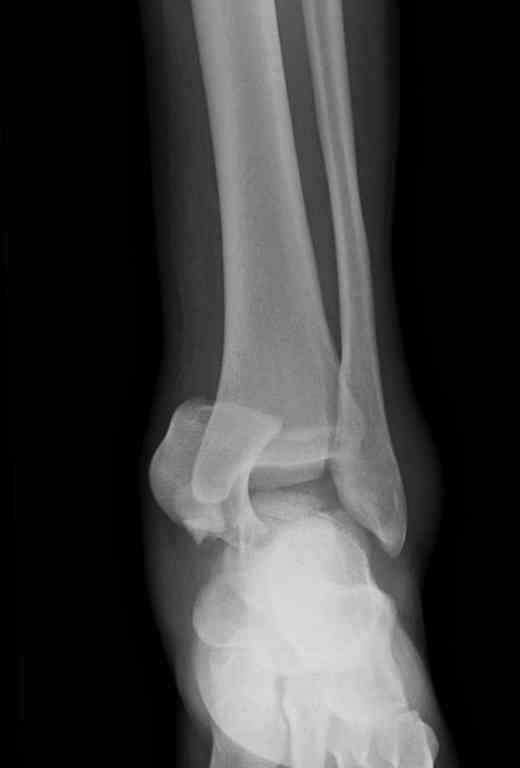

Второй случай прооперирован вчера.

10 дней назад поступил с открытым повреждением медиальной лодыжки и переломо вывихом таранной кости. Ургентно сделана репозиция с наложением наружного фиксатора + Irrigation&Debridment.

Из-за многооскольчатости дистальной части малоберцовой, где невозможно было провести фиксацию шурупами, перелом зафиксирован подпирающей пластиной, которая должна служить дополнением отсутствующей дистальной части малоберцовой (lateral cortex substitute).

Для стабильности два шурупа на синдесмоз.

Медиальную рану с приближенными краями продолжаем вакуумировать (KCI). Наружный фиксатор оставлен на пару недель, надеюсь, небольшая рана будет гранулировать и закроется без кожной пластики. Фиксация медиальной ложыжки не планируется.